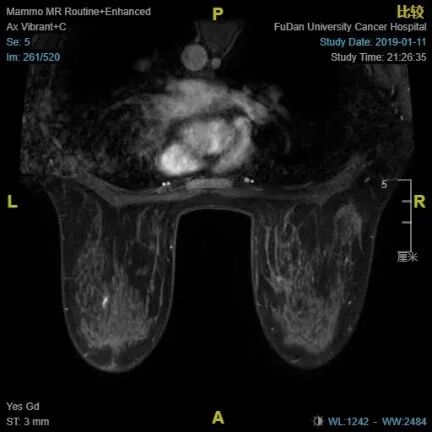

4疗程治疗后评估:CR

4疗程后MRI:右乳癌治疗后较前好转,BI-RADS:6。 右腋下小淋巴结同前

问题三、4疗程治疗后选择:评估为CR,手术还是继续新辅助化疗

临床实践中,我们推荐新辅阶段每两个疗程做一次疗效评估,如果C2或C4评估时,新辅疗效不佳,建议更换新辅治疗方案或者直接手术,并术后更换治疗方案。对于该患者,当经历过4疗程新辅助治疗后取得CR的疗效,建议及时手术,以避免患者之后进一步进展的风险;该名患者术前乳腺的核磁检查等,没有看到任何广泛性的病灶,术前穿刺也做了一个Clip的定位夹,情况符合新辅后保乳手术的指征,并且虽然影像学上有腋窝淋巴结,但是穿刺也没有看到,可以考虑做右腋窝前哨淋巴结活检术。